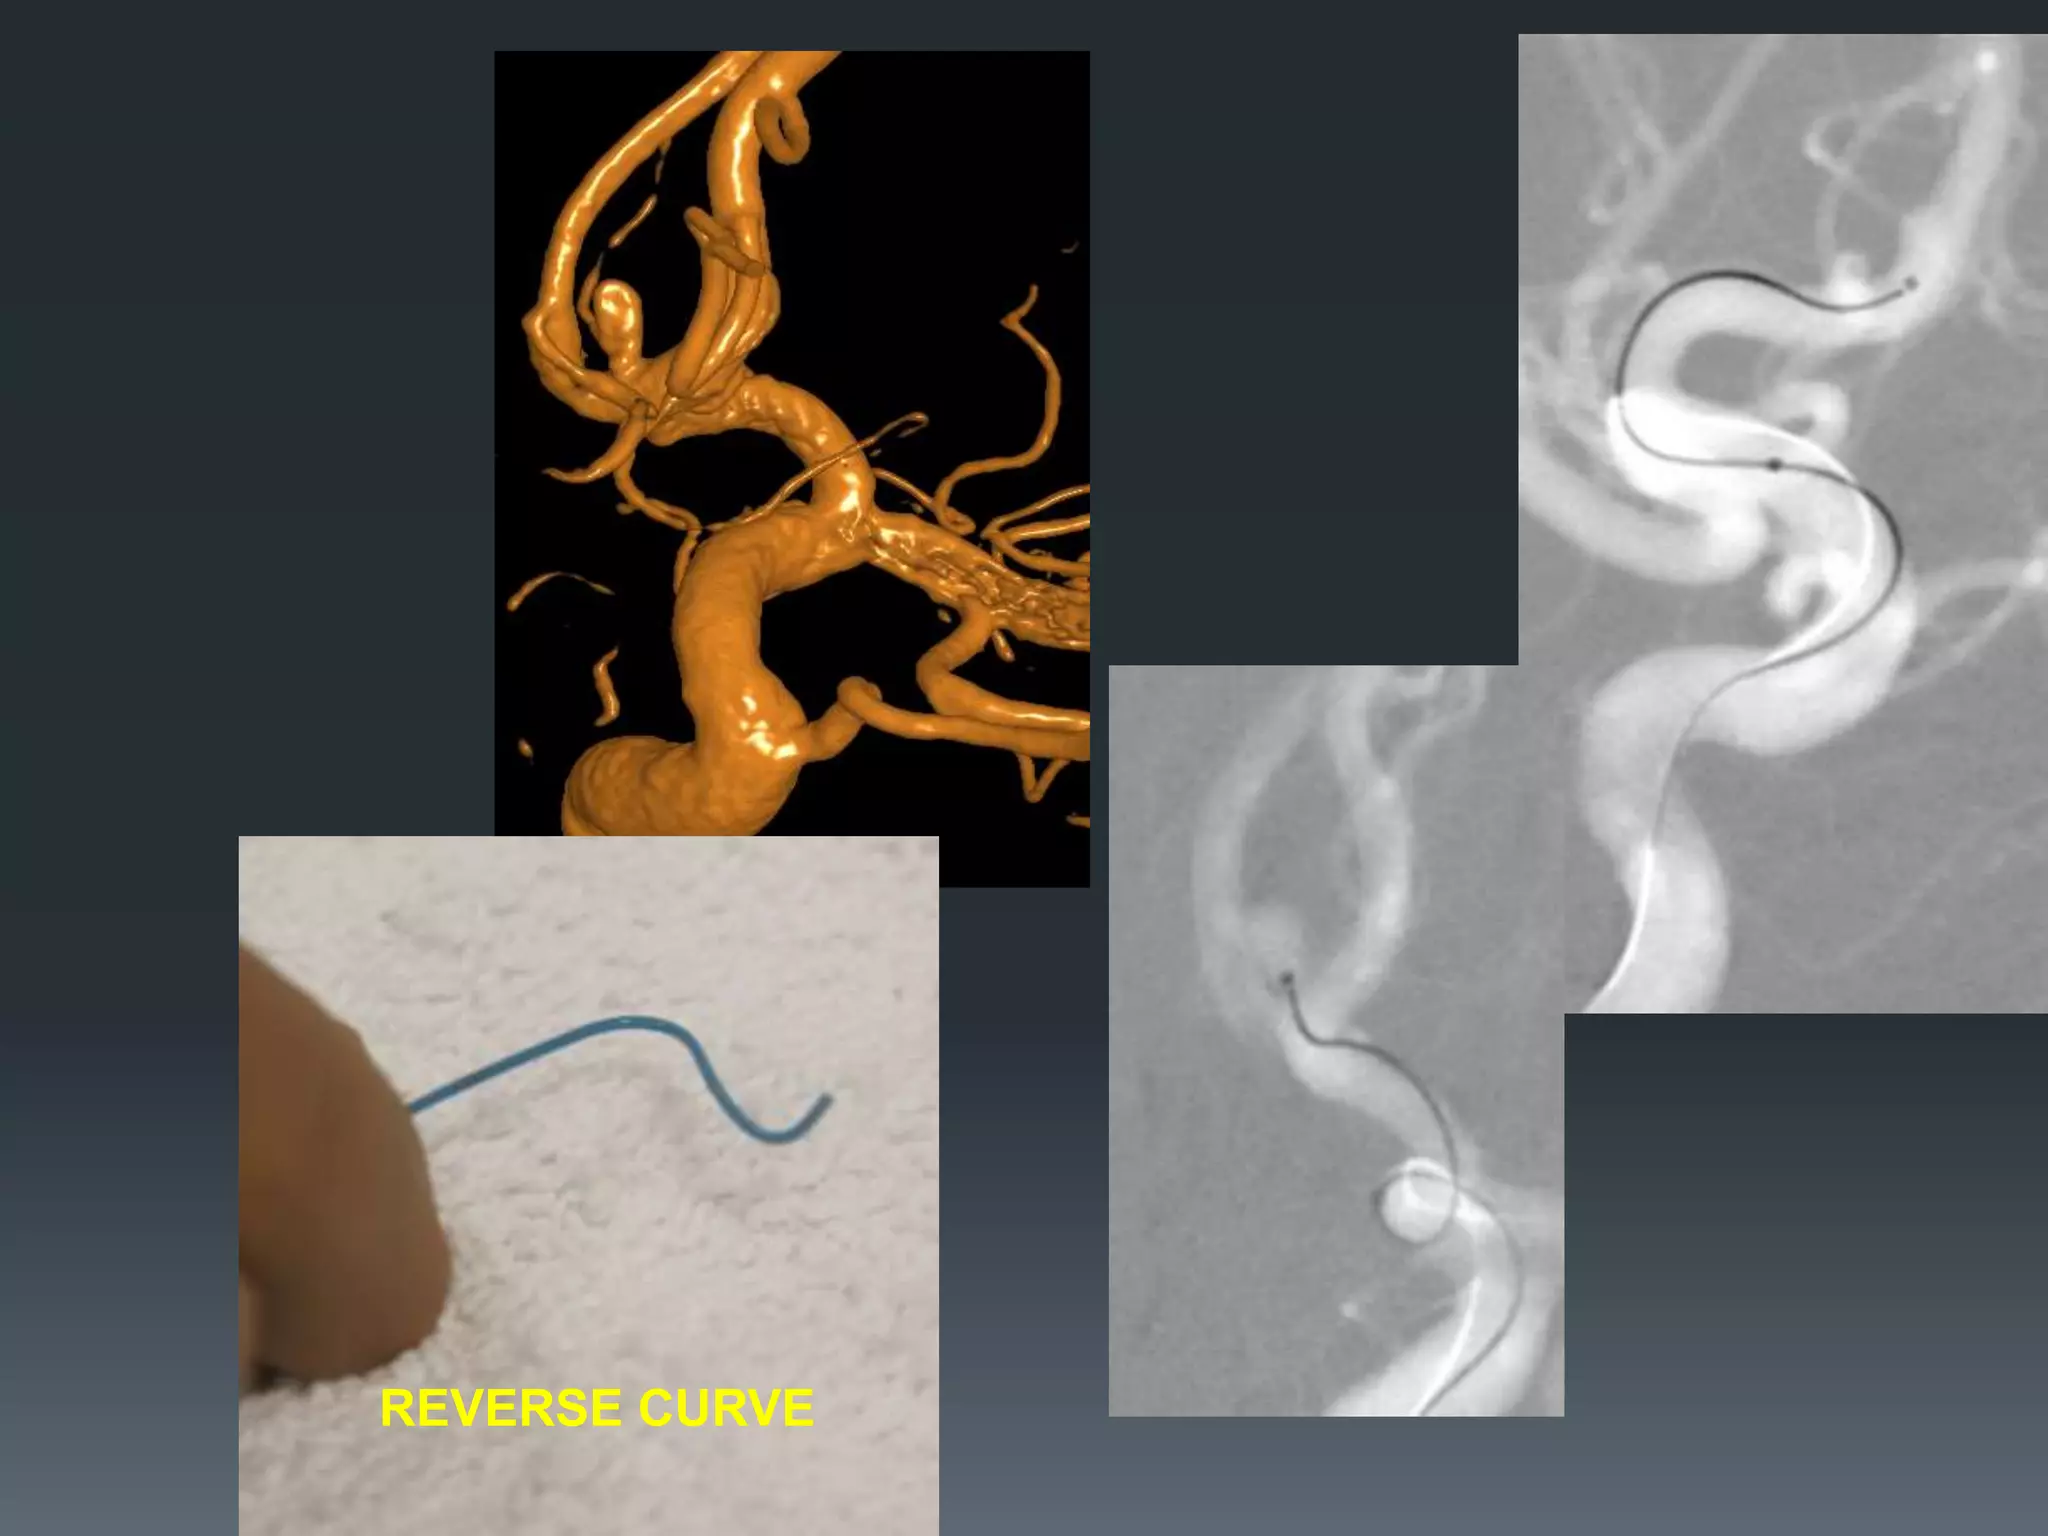

This document discusses tricks and techniques for difficult cannulations during neurointerventional procedures. It outlines strategies for accessing the aortic arch, internal carotid artery (ICA), and areas distal to aneurysms. Long sheaths, distal access catheters, and co-axial techniques are presented as options that have improved cannulation success. Guidance on sheath and catheter selection is provided for different vessel paths. The importance of catheter placement as high as possible in the ICA is emphasized. Reverse curve cannulations are also mentioned. Overall, the document stresses that careful cannulation is critical for procedural success and different strategies may be needed depending on the vessel target.